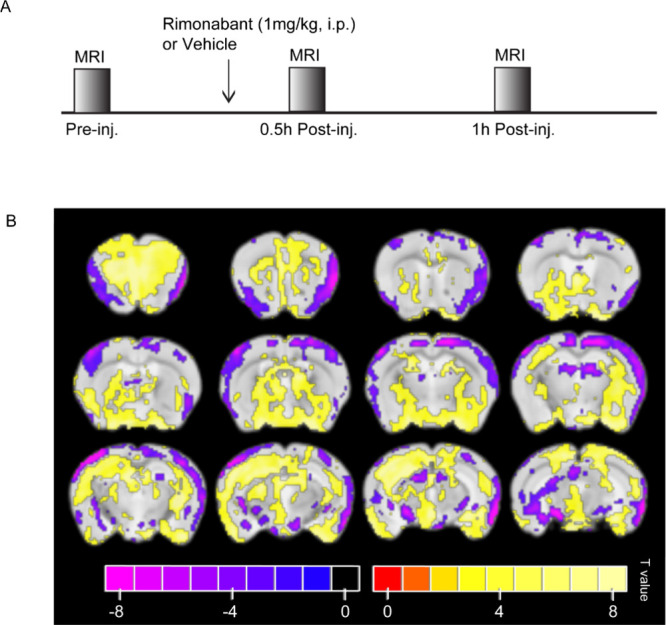

Using a recent high-sensitivity method of generating statistical brain activation maps,36 we identified the parts of the brain where an effect had occurred a certain amount of time after administering the vehicle or rimonabant (first level) and where there was a difference between the drug and vehicle’s first level results (second level). The scheme of mouse drug challenge and MR scanning timeline are shown in Figure A. We collected EPI images immediately prior to the drug injection as well as at 30 and 60 min after the injection. As results may not have been stable at 30 min,37 we focused on results at 60 min. The second level map of statistically significant T values 60 min after the rimonabant or vehicle injection is shown in Figure B.

At 60 min after injection, many regions with both significant positive and significant negative activations can be observed. Regions that included at least 100 voxels of positive activation were the secondary motor areas (layers 2, 3, and 5), the Hippocampus (subregions CA1 and CA3), the molecular layer of the dentate gyrus, the caudoputamen, the medial amygdalar nucleus, and the olfactory tubercle and main olfactory bulb. Regions that included at least 100 voxels of negative activation were the primary somatosensory areas (layers 2–3), the midbrain reticular nucleus, and periaqueductal gray matter. Regions that included both at least 100 voxels of positive and 100 voxels of negative activation were the piriform area and the midbrain. (Possibly unstable) Results 30 min after injection showed positive activation across almost the entire brain, with the exception of entorhinal areas, which had negative activation (Figure S4).